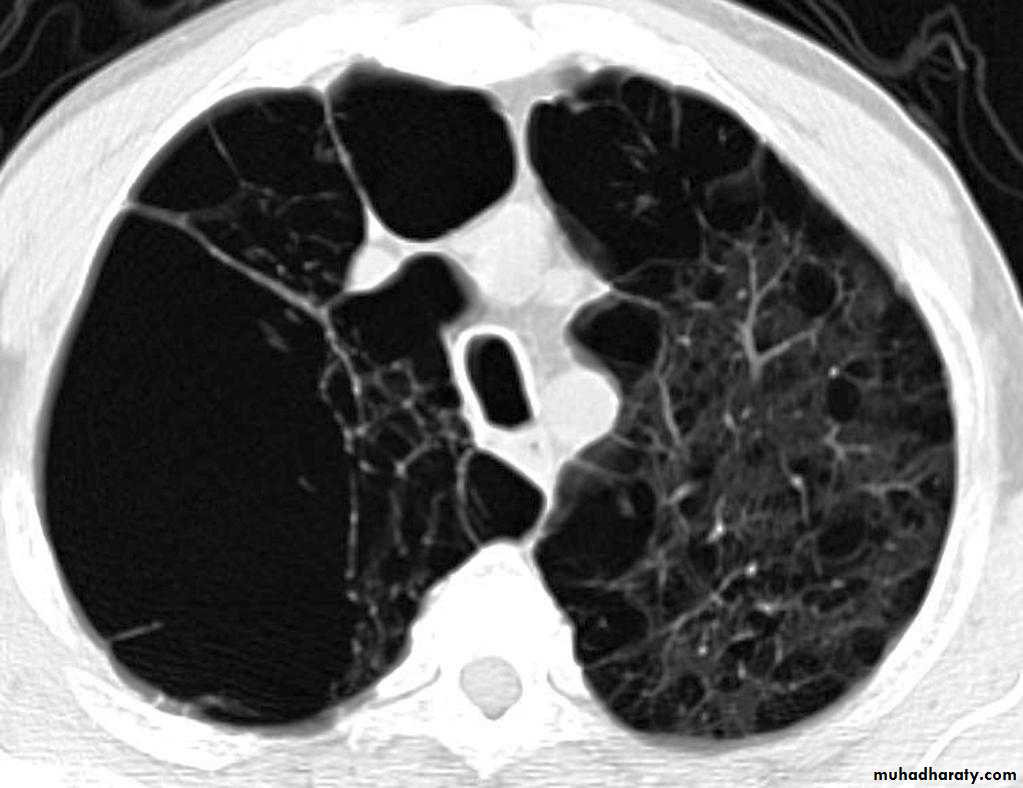

Pulmonary emphysema is defined as the "abnormal permanent enlargement of the airspaces distal to the terminal bronchioles accompanied by destruction of the alveolar wall and without obvious fibrosis". Emphysema is one of the entities grouped together as chronic obstructive pulmonary diseaseRadiographic features

Plain filmExcept in the case of very advanced disease with bulla formation, chest radiography does not image emphysema directly, but rather infers the diagnosis due to associated features :

hyperinflation:

1.flattened hemidiaphragm(s): most reliable sign

2.ncreased and usually irregular radiolucency of the lungs

9.vascular changes paucity of blood vessels ( absent pulmonary markings in outer 1/3 of the lung fields )